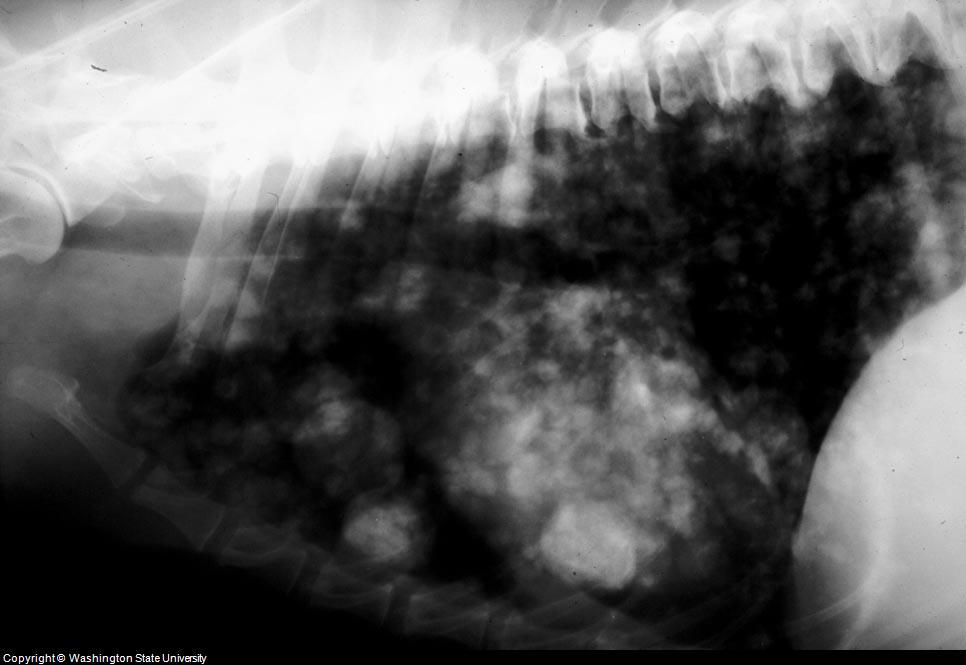

Dog Lung Cancer Canine Lung Tumors Michigan Ave Animal Hospital